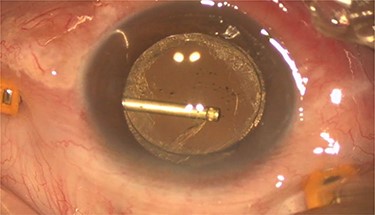

Pars plana vitrectomy and posterior capsulotomy were done. After placing three 23-gauge trocars, a corneal paracentesis was made. After IOL tapping, the entrapped turbid fluid escaped to the anterior chamber (Fig. 3). Anterior vitrectomy and posterior capsulotomy were done using a 23-gauge vitrector (Fig. 4).

Intra-operative photo showed egression of turbid fluid to the anterior chamber.